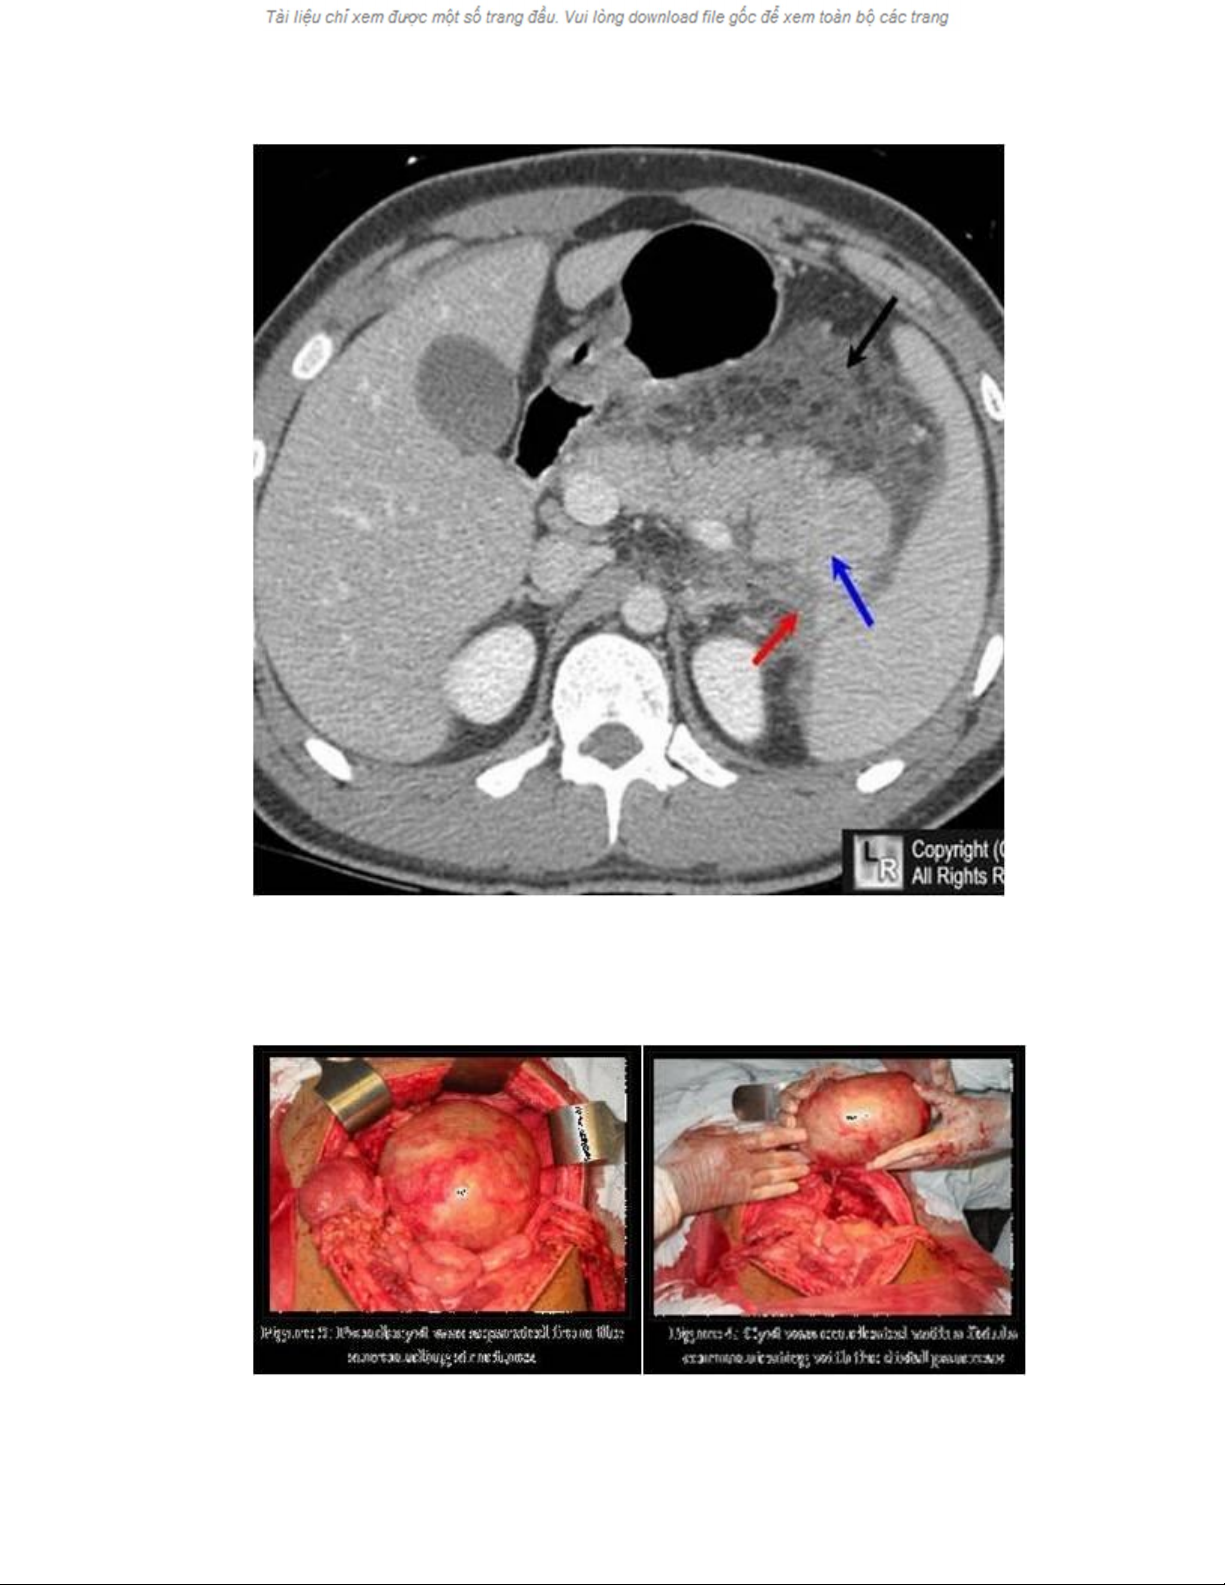

Viêm tuỵ hoại tử

Hình ảnh nang giả tuỵ trên CAT-scan